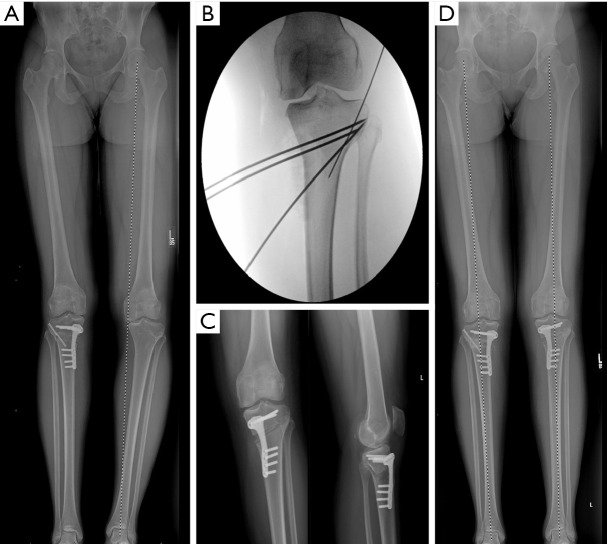

膝关节周围截骨术是一种有效的方法,通过纠正膝关节的整体排列来保护膝关节。虽然截骨术历来被用于治疗膝关节病理,但最近作为一种治疗策略重新引起了人们的兴趣,这种治疗策略可用于矫正关节位、韧带稳定和软骨保护。截骨术是纠正矢状面和冠状面排列的一种有效方法,可以保存和/或保护膝关节内侧、外侧和髌股间室的软骨,并改善膝关节韧带的稳定性。内侧开口楔形高胫骨截骨术(MOW-HTO)和外侧闭合楔形高胫骨截骨术(LCW-HTO)是矫正内翻畸形的常用截骨术,各有不同的适应症、手术技术和相关并发症。同样,股骨远端截骨术(DFO)在矫正内翻和外翻错位中起着至关重要的作用,在单独胫骨截骨术会导致关节线倾斜度过高(JLO)的情况下可能尤为重要。在单节段截骨不能提供最佳矫正的复杂情况下,可能需要双节段截骨来实现适当的机械轴修复,同时保持关节一致性。除了冠状面矫正外,矢状面截骨术越来越受到关注,以治疗韧带不稳定,特别是前后交叉韧带(PCL)缺陷。通过前闭合楔形或前开放楔形高位胫骨截骨术改变胫骨后斜率(PTS)可以改善前交叉韧带(ACL)和pcl缺陷患者的膝关节生物力学和稳定性。此外,胫骨结节截骨术(TTO)已成为一种重要的手术辅助治疗髌骨股骨错位和软骨保存策略。膝关节截骨术的目的是卸载受影响的腔室,保存和保护软骨和半月板,增强韧带的稳定性,从而推迟关节置换术的需要。因此,截骨术对于年轻和活跃的患者来说是一种有趣的手术。最近,随着对膝关节截骨术的重新关注,研究表明,截骨术在肢体对齐和软骨保护治疗中继续发挥关键作用。

Osteotomies around the knee are an effective method for preserving the knee joint by correcting overall alignment. Although osteotomies have historically been used in treatment of knee pathology, they have recently regained a renewed interest as a treatment strategy for alignment correction, ligamentous stability, and cartilage preservation. Osteotomies are a powerful way to correct alignment in both the sagittal and coronal plane to preserve and/or protect the cartilage in the medial, lateral, and patellofemoral compartments of the knee and improve the ligamentous stability of the knee. Medial opening wedge high tibial osteotomy (MOW-HTO) and lateral closing wedge high tibial osteotomy (LCW-HTO) are commonly performed osteotomies for correcting varus malalignment, each with distinct indications, surgical techniques, and associated complications. Similarly, distal femoral osteotomy (DFO) plays a critical role in the correction of both varus and valgus malalignment, and may be particularly important in cases where a tibial osteotomy alone would lead to excessive joint line obliquity (JLO). In complex cases where single-level osteotomy does not provide optimal correction, double-level osteotomy may be necessary to achieve appropriate mechanical axis restoration while maintaining joint congruence. Beyond coronal plane corrections, increasing attention has been given to sagittal plane osteotomies for managing ligamentous instability, particularly anterior and posterior cruciate ligament (PCL) deficiencies. Modifying the posterior tibial slope (PTS) through anterior closing wedge or anterior opening wedge high tibial osteotomy can improve knee biomechanics and stability in both anterior cruciate ligament (ACL) and PCL-deficient patients. Additionally, tibial tubercle osteotomies (TTO) have emerged as an important surgical adjunct in the treatment of patellofemoral malalignment and cartilage preservation strategies. The goal of knee osteotomies is to offload the affected compartment, preserve and protect cartilage and menisci, and enhance ligamentous stability, thereby delaying the need for arthroplasty. Therefore, osteotomies represent an intriguing procedure for young and active patients. Recently, with the renewed interest in osteotomy procedures about the knee, studies have demonstrated that osteotomies continue to play a critical role in treatments for limb alignment and cartilage protection.